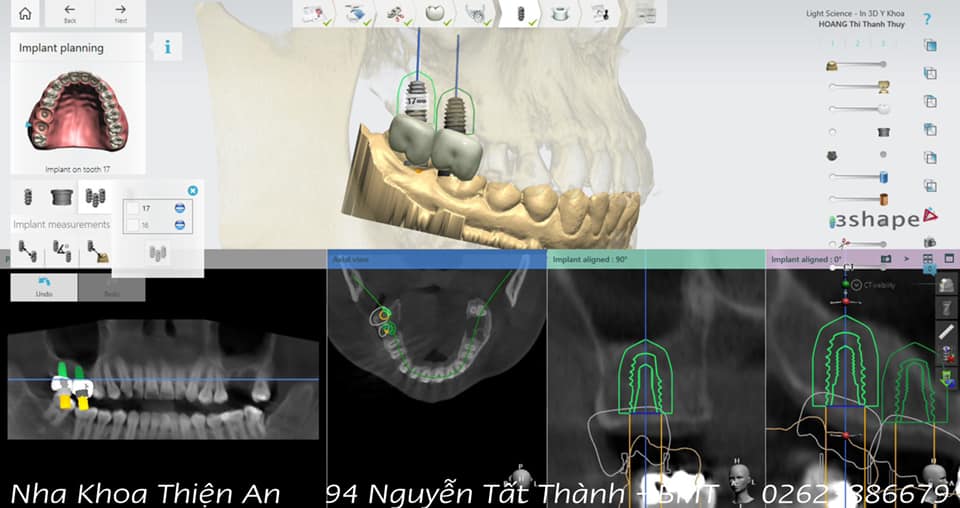

Tiếp tục là những ca cấy ghép implant nhẹ nhàng, không đau, hạn chế xâm lấn tại nha khoa Thiện An BMT – Đăk Lăk do BS. CK2 Huỳnh Thanh Trung trực tiếp thực hiện

Cấy ghép implant là kỹ thuật trồng răng giả bằng cách cấy vào xương hàm tại vị trí chân răng cũ một chiếc chân răng nhân tạo, sau đó trồng lên chân răng một chiếc răng khác thay thế răng đã mất phục vụ cho mục đích thẩm mỹ hoặc ăn nhai

Continued to be gentle, painless, minimally invasive implant cases at Thien An BMT Dental Clinic – Dak Lak by Dr. CK2 Huynh Thanh Trung directly performed

Implant is a technique of planting false teeth by implanting an artificial tooth root into the jawbone at the old tooth root position, then planting another tooth on the root to replace the lost tooth for aesthetic purposes. or chew